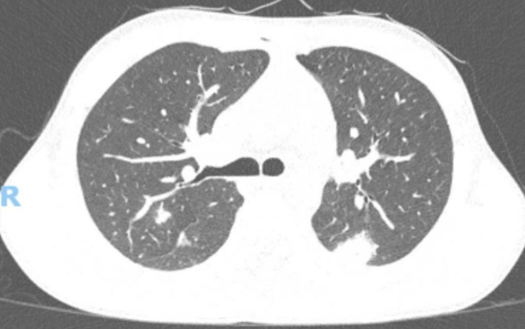

The Crack Lung – A Case Report

Débora Lopes, Cátia Gorgulho, Joana Ribeiro, André Neto Real, Nuno Catorze

bjcr49